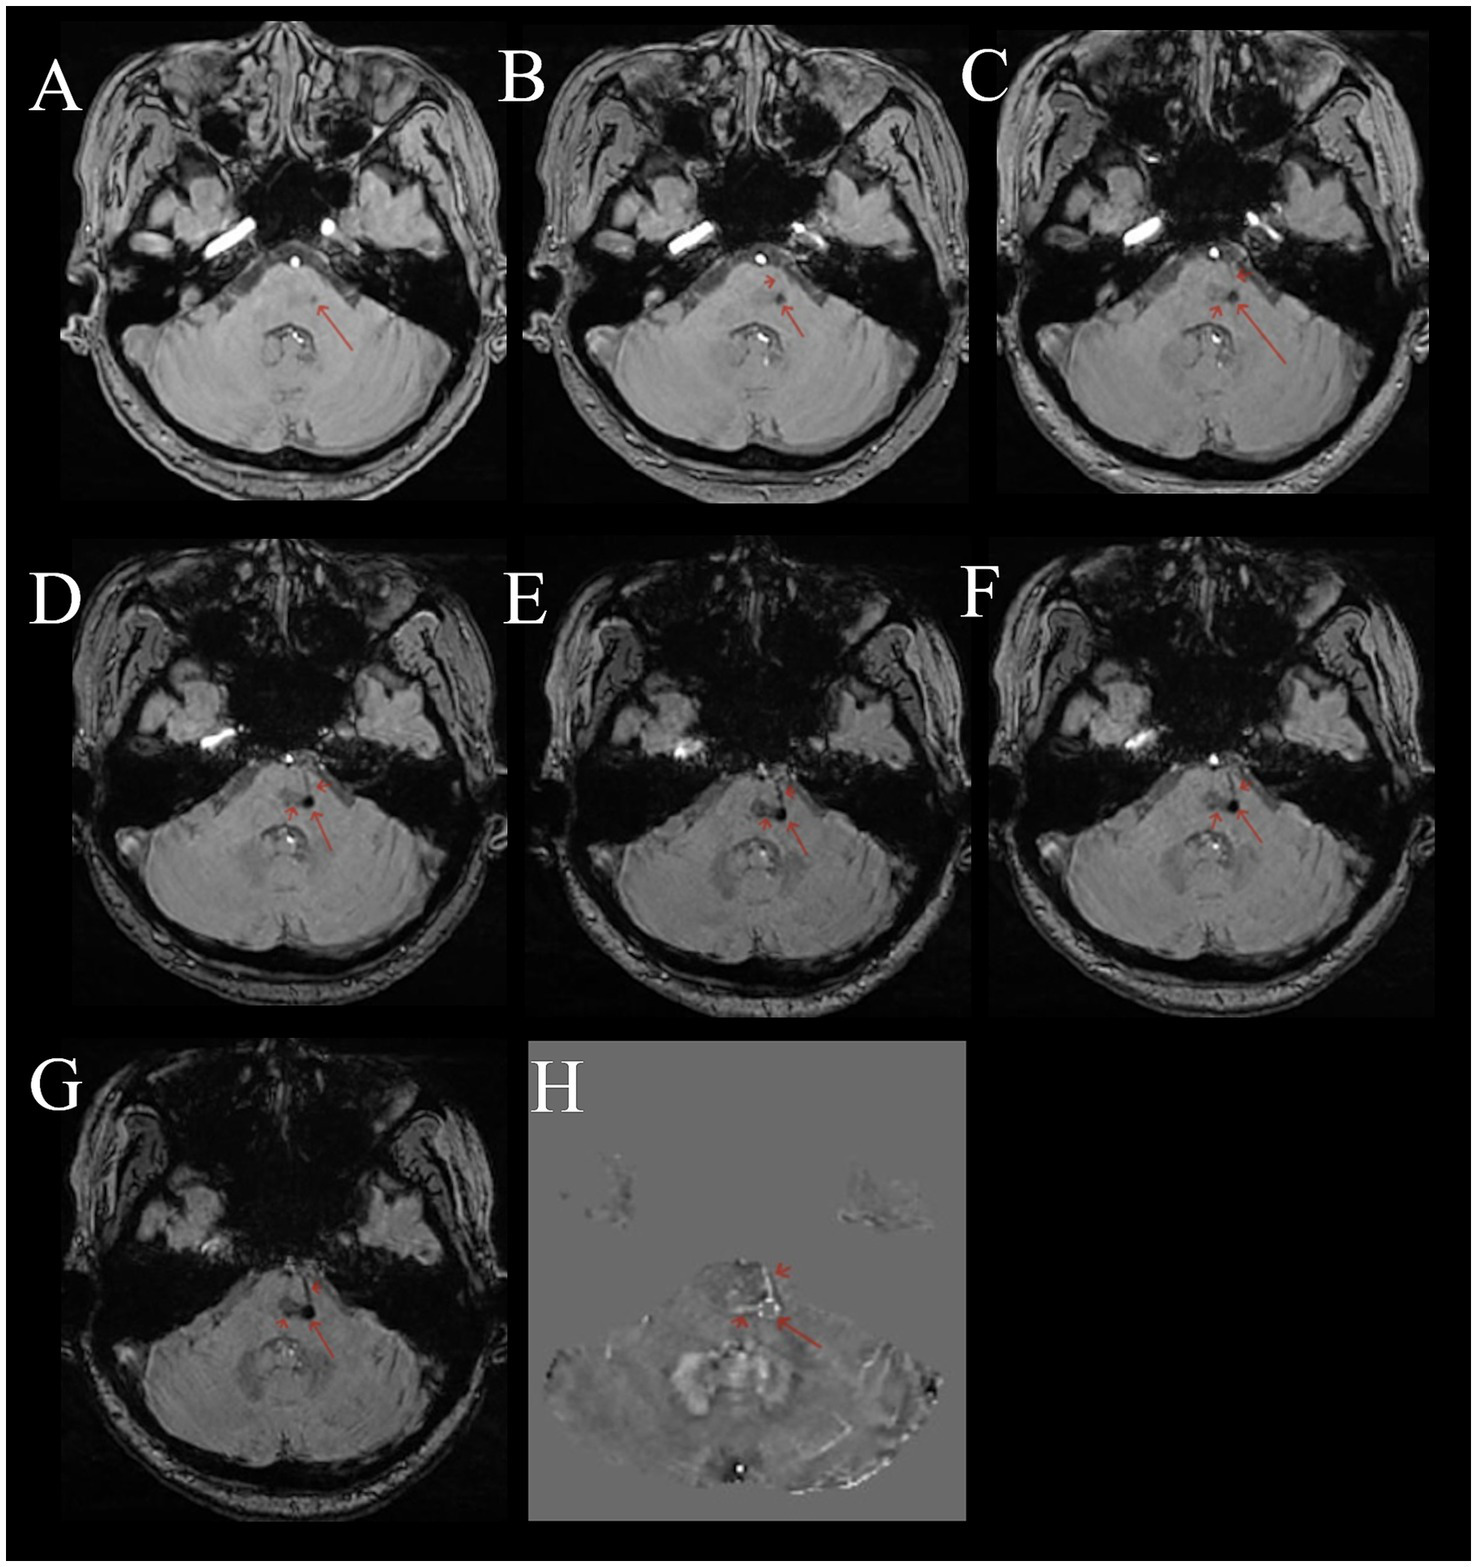

Compared to normal or other disease (see Supplementary material), on multi-echo SWI with long TE (22.5 ms), BCT lesions all presented as distinct small round hypointense signals on images, with punctate or strip-like slightly hyperintense signals at the center and a hypointense ring at the edge, forming a typical “single-ring target sign” (long red arrows in Figures 1A–D, 2A–G). Lesions had clear boundaries, and increased and thickened draining small veins were visible around the lesions (short red arrows in Figures 1A–D, 2A–G). QSM images showed round abnormal signals of lesions, with the central part being hyperintense due to the passage or penetration of central veins, a hypointense ring in the middle, and slightly hyperintense or hyperintense signals at the outermost edge, forming the most typical “double-ring target sign” (long red arrow in Figure 1E). The edges of some lesions showed a slightly hyperintense ring, and the inner side showed a hypointense ring, forming a typical “target sign” (dashed red arrow in Figure 1E). Meanwhile, increased and thickened small veins were observed around the lesions (short red arrows in Figures 1E, 2H). Some lesions only showed punctate hyperintense signals (solid long red arrow in Figure 1E). DWI, Flair, and T1WI images showed a few punctate hypointense signals (short red arrows in Figures 1F,H,I), and ADC showed punctate hyperintense signals (Figure 1G).

Figure 1

Male, 73 years old, with right limb motor impairment for 15 years and dizziness for 1 day. (A) Phase map. (B) Amplitude map. (C) SWI image. (D) MinIP image with TE of 22.5 ms. (E) QSM image. (F) DWI image. (G) ADC map. (H) FLAIR image. (I) T1WI image. (A–D) Round-like hypointense signals can be seen in the left periventricular region and the left parietal cortex, with hyperintense signals in the center, forming a typical “target sign” (long red arrow). The surrounding lesions show hypointense signals from the drainage of the left subependymal vein and parietal cortical vein (short red arrow). (E) QSM shows two round-like abnormal signals in the left periventricular region. The central part is the hyperintense central vein, the middle is hypointense, and the outermost edge is slightly hyperintense or hyperintense, forming the most typical “target sign” (long red arrow). The surrounding lesions have strip-like hyperintense subependymal vein drainage (short red arrow) passing through two BCTs (long red arrow). The left parietal cortex shows round-like lesions with hypointense in the center and hyperintense at the edge, forming a typical “target sign” (dashed long line). (F) DWI image, showing punctate hypointense signals in the left periventricular region and parietal cortex (short red arrow). (G) Shows slightly hyperintense signals. (H) Shows hypointense signals (short red arrow). (I) T1WI image, showing slightly hypointense signals.